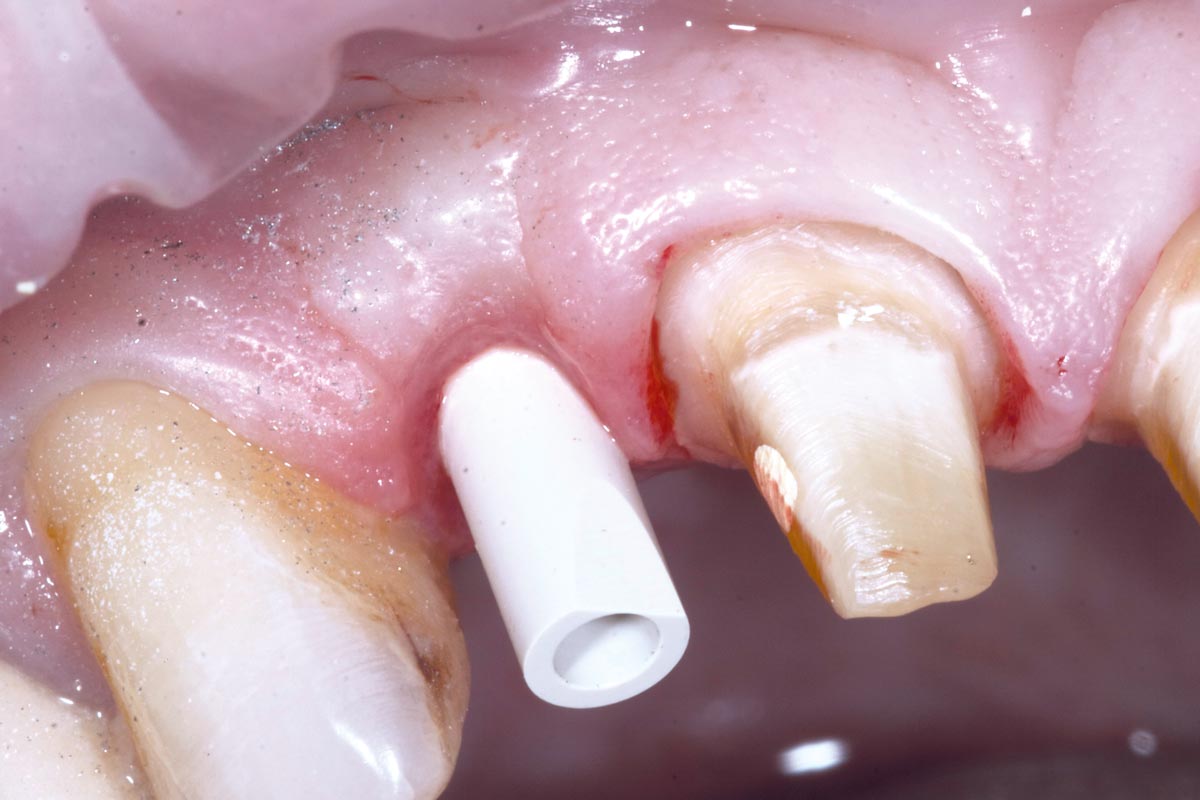

3/19 - Fracture of tooth while extractionBone augementation with maxresorb® - Dr. R. Cutts